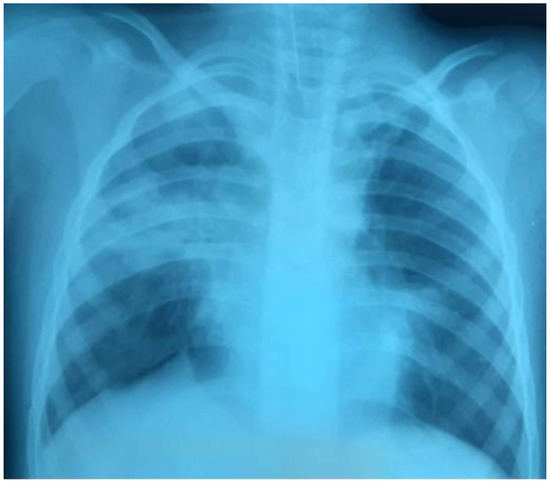

Clinical Characteristics and Quality of Life of Persistent Symptoms of COVID-19 Syndrome in Indonesia

by Agus Dwi Susanto, Fathiyah Isbaniah, Irandi Putra Pratomo, Budhi Antariksa, Erlang Samoedro, Muhammad Taufik, Fadlika Harinda and Fariz Nurwidya

Introduction: Coronavirus disease-2019 (COVID-19), caused by the severe acute respiratory syndrome coronavirus-2 (SARS-CoV-2) manifests in a broad clinical spectrum. COVID-19 survivors report various symptoms up to several months after being infected. The purpose of this study was to determine the prevalence of persistent COVID-19 syndrome in Indonesia, the factors that influence the incidence, and the quality of life. Methods: This was a cross-sectional study with an online questionnaire conducted in January 2021. Inclusion criteria were: adult Indonesian citizens who had recovered from COVID-19, and were confirmed negative by RT-PCR of nasal swabs or had undergone an isolation period for a minimum of 14 days. Data analysis was performed by the Chi-square test, followed by multivariate analysis with the backward likelihood ratio method. Results: From a total of 385 respondents, 256 (66.5%) experienced persistent COVID-19 syndrome. The most prevalent symptoms were fatigue (29.4%), cough (15.5%), and muscle pain (11.2%). Of the five aspects of quality of life, the most commonly reported aspects were pain/discomfort and anxiety/depression. The risk of persistent COVID-19 syndrome was significantly higher in subjects with older age, comorbidities, higher clinical severity, previous treatment in hospital, presence of pneumonia, and those who had required oxygen therapy. In the multivariate analysis, the most influential factor for the incidence of persistent COVID-19 syndrome was pneumonia (aOR 2.31, 95% CI 1.29–4.11, p < 0.002). Conclusions: The prevalence of the persistent COVID-19 syndrome in Indonesia was high, which affects the quality of life of COVID-19 survivors. Pneumonia was the main factor that influenced the incidence of persistent COVID-19 syndrome. Further research with a larger sample size and a longer study time is recommended to control COVID-19 and its impact on the health and quality of life of COVID-19 survivors. Full article

Show Figures